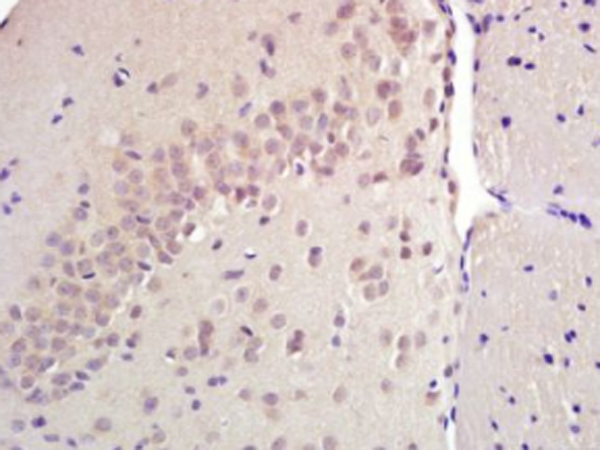

IHC positive control: |

rat adrenal gland and rat brain |

IHC Recommend dilution: |

30-150 |